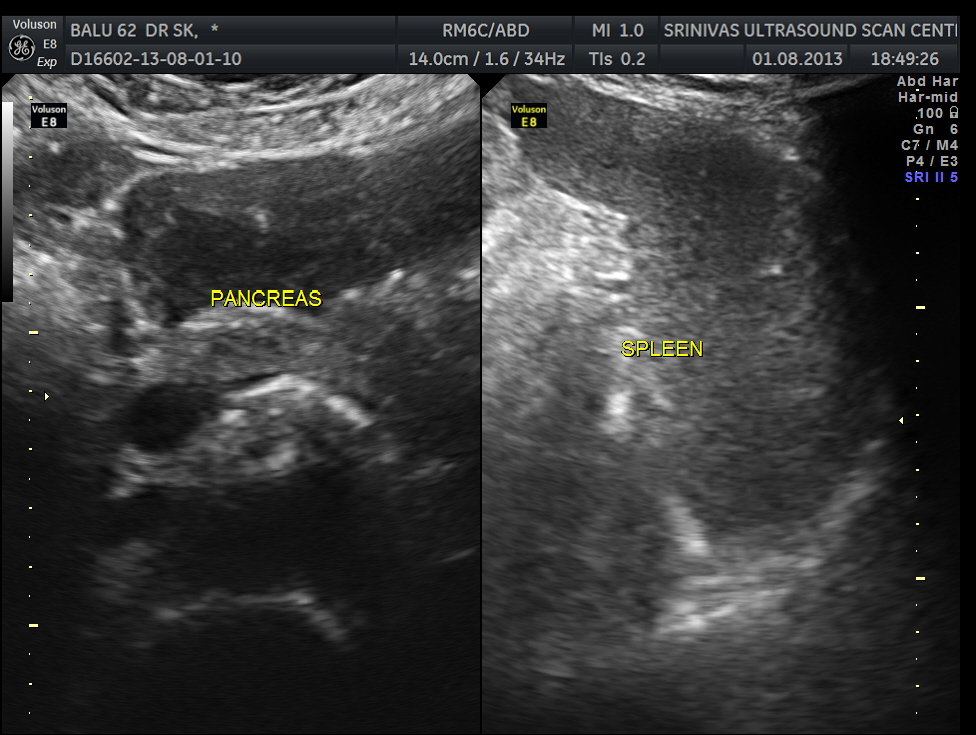

Clinically he had uncontrolled systemic hypertension and mildly elevated s. creatinine of 1.7 mgms/dl.

The diagnosis offered was multiple liver secondaries with incidental finding of shrunk right kidney with probable reduced function.